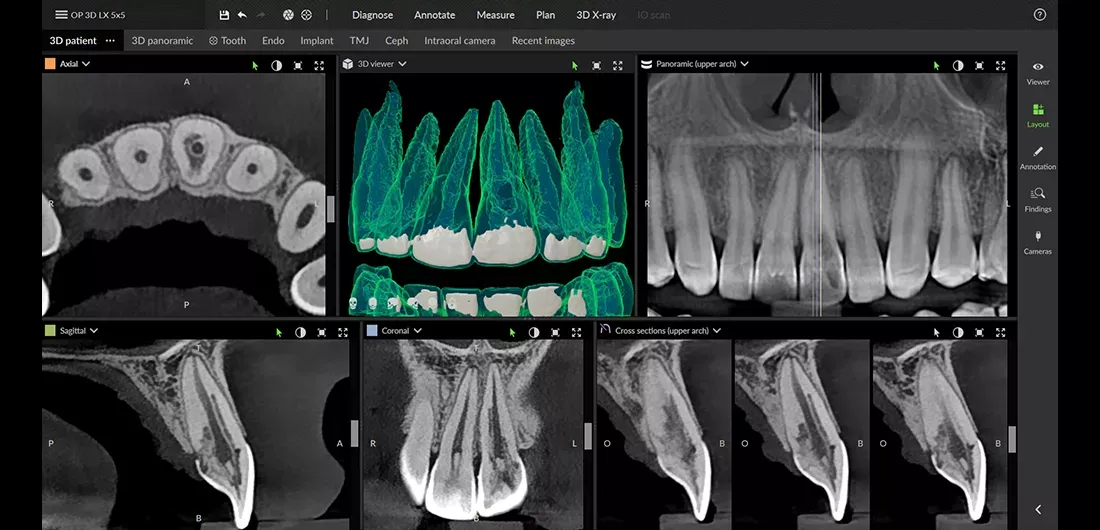

Pierwszym i podstawowym narzędziem diagnostycznym, które pozwala mi wstępnie ocenić anatomię zęba, jest zdjęcie rentgenowskie (RTG). Dzięki niemu mogę zobaczyć liczbę i kształt korzeni, a także zarys kanałów. To niezbędny punkt wyjścia, który daje ogólny obraz sytuacji.

Tomografia komputerowa (CBCT) kiedy potrzebujemy obrazu 3D?

W szczególnie skomplikowanych przypadkach, gdy mam do czynienia z nietypową anatomią, zrostami korzeni czy podejrzeniem dodatkowych, trudno dostępnych kanałów, sięgam po tomografię komputerową wiązki stożkowej (CBCT). To zaawansowane badanie pozwala na wizualizację kanałów w trzech wymiarach, co jest niemożliwe na tradycyjnym RTG. Obraz 3D jest nieoceniony w planowaniu leczenia i pozwala mi przygotować się na wszelkie niespodzianki anatomiczne.